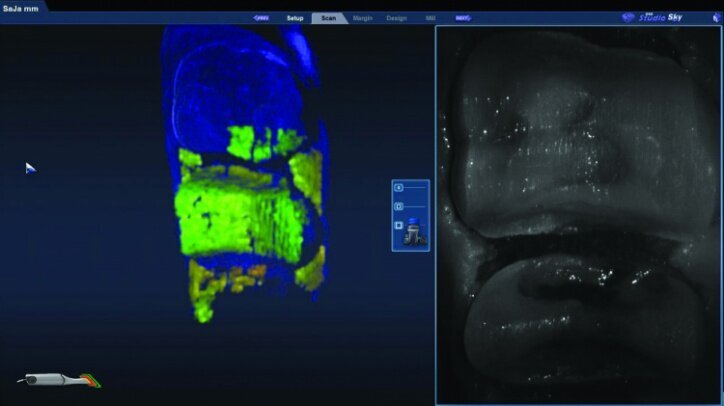

While waiting four minutes for gingival retraction, the opposing teeth were scanned with the PlanScan wand to create a digital model (Figs. 22a–24c). The buccal surfaces were then scanned with the teeth fully occluded in maximum intercuspal position. This scan was used along with the scan of the preparations and the opposing teeth to create a model for the occlusion (Figs. 25a–26c).

Prior to scanning the prepared teeth, the second cords were rinsed and removed. The cords were left wet to lower the risk of disturbing the tissue upon removal. The #00 cords were left in place during the scanning of the preparations, and the teeth were dried to allow accurate scanning.

The preparation model was examined in data density view to verify adequate data was obtained during the scanning of the preparations (Fig. 26c).

Any areas lacking adequate data were scanned further until adequate data was obtained. Next, orientation of the preparation model was performed (Fig. 26d). Orientation is for optimal design, not path of insertion. The margins were then traced and viewed in ICE mode, which provides a rendering of the scanned images for a clear view of the margins, teeth and tissues (Figs. 26e, f).